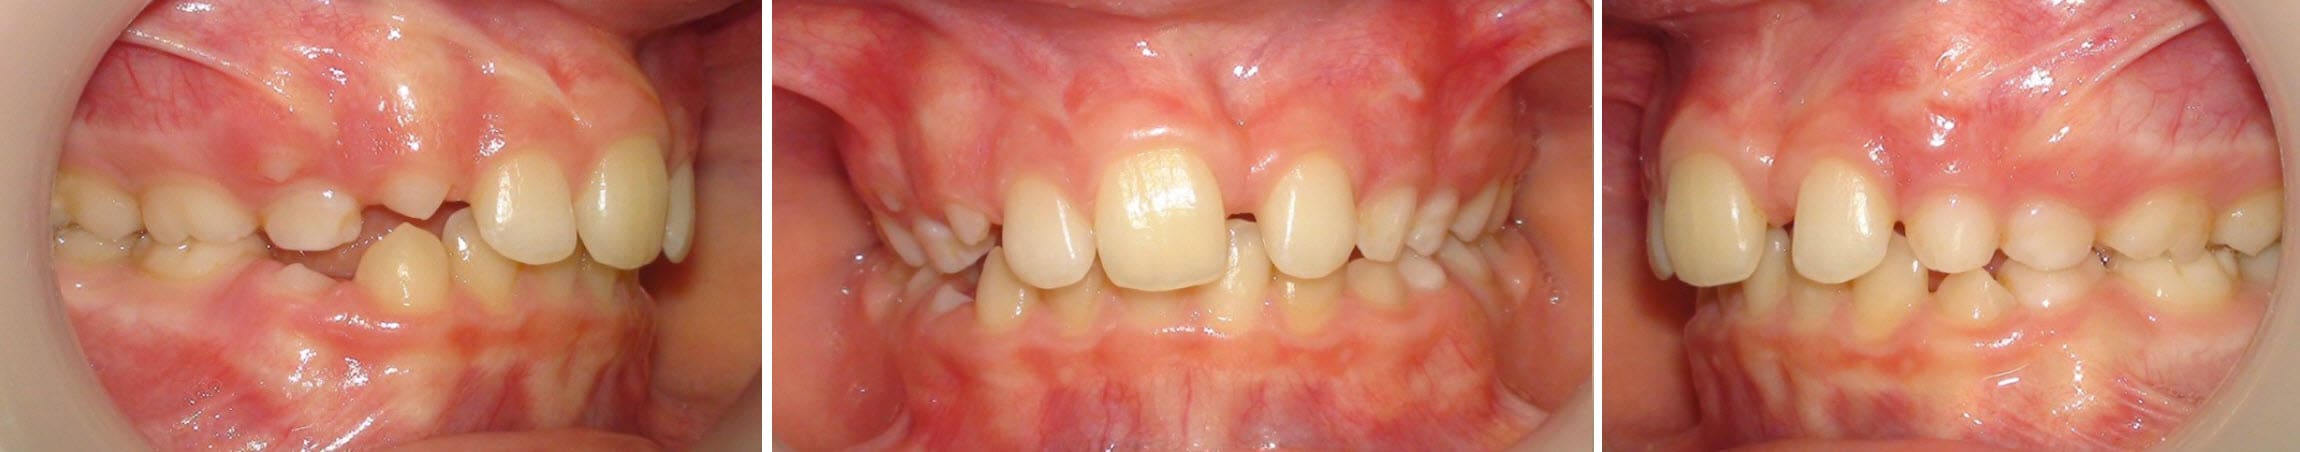

Voici les clichés radios demandés. Cette jeune fille a 7 ans.

Qu'est-ce que tu proposes ?